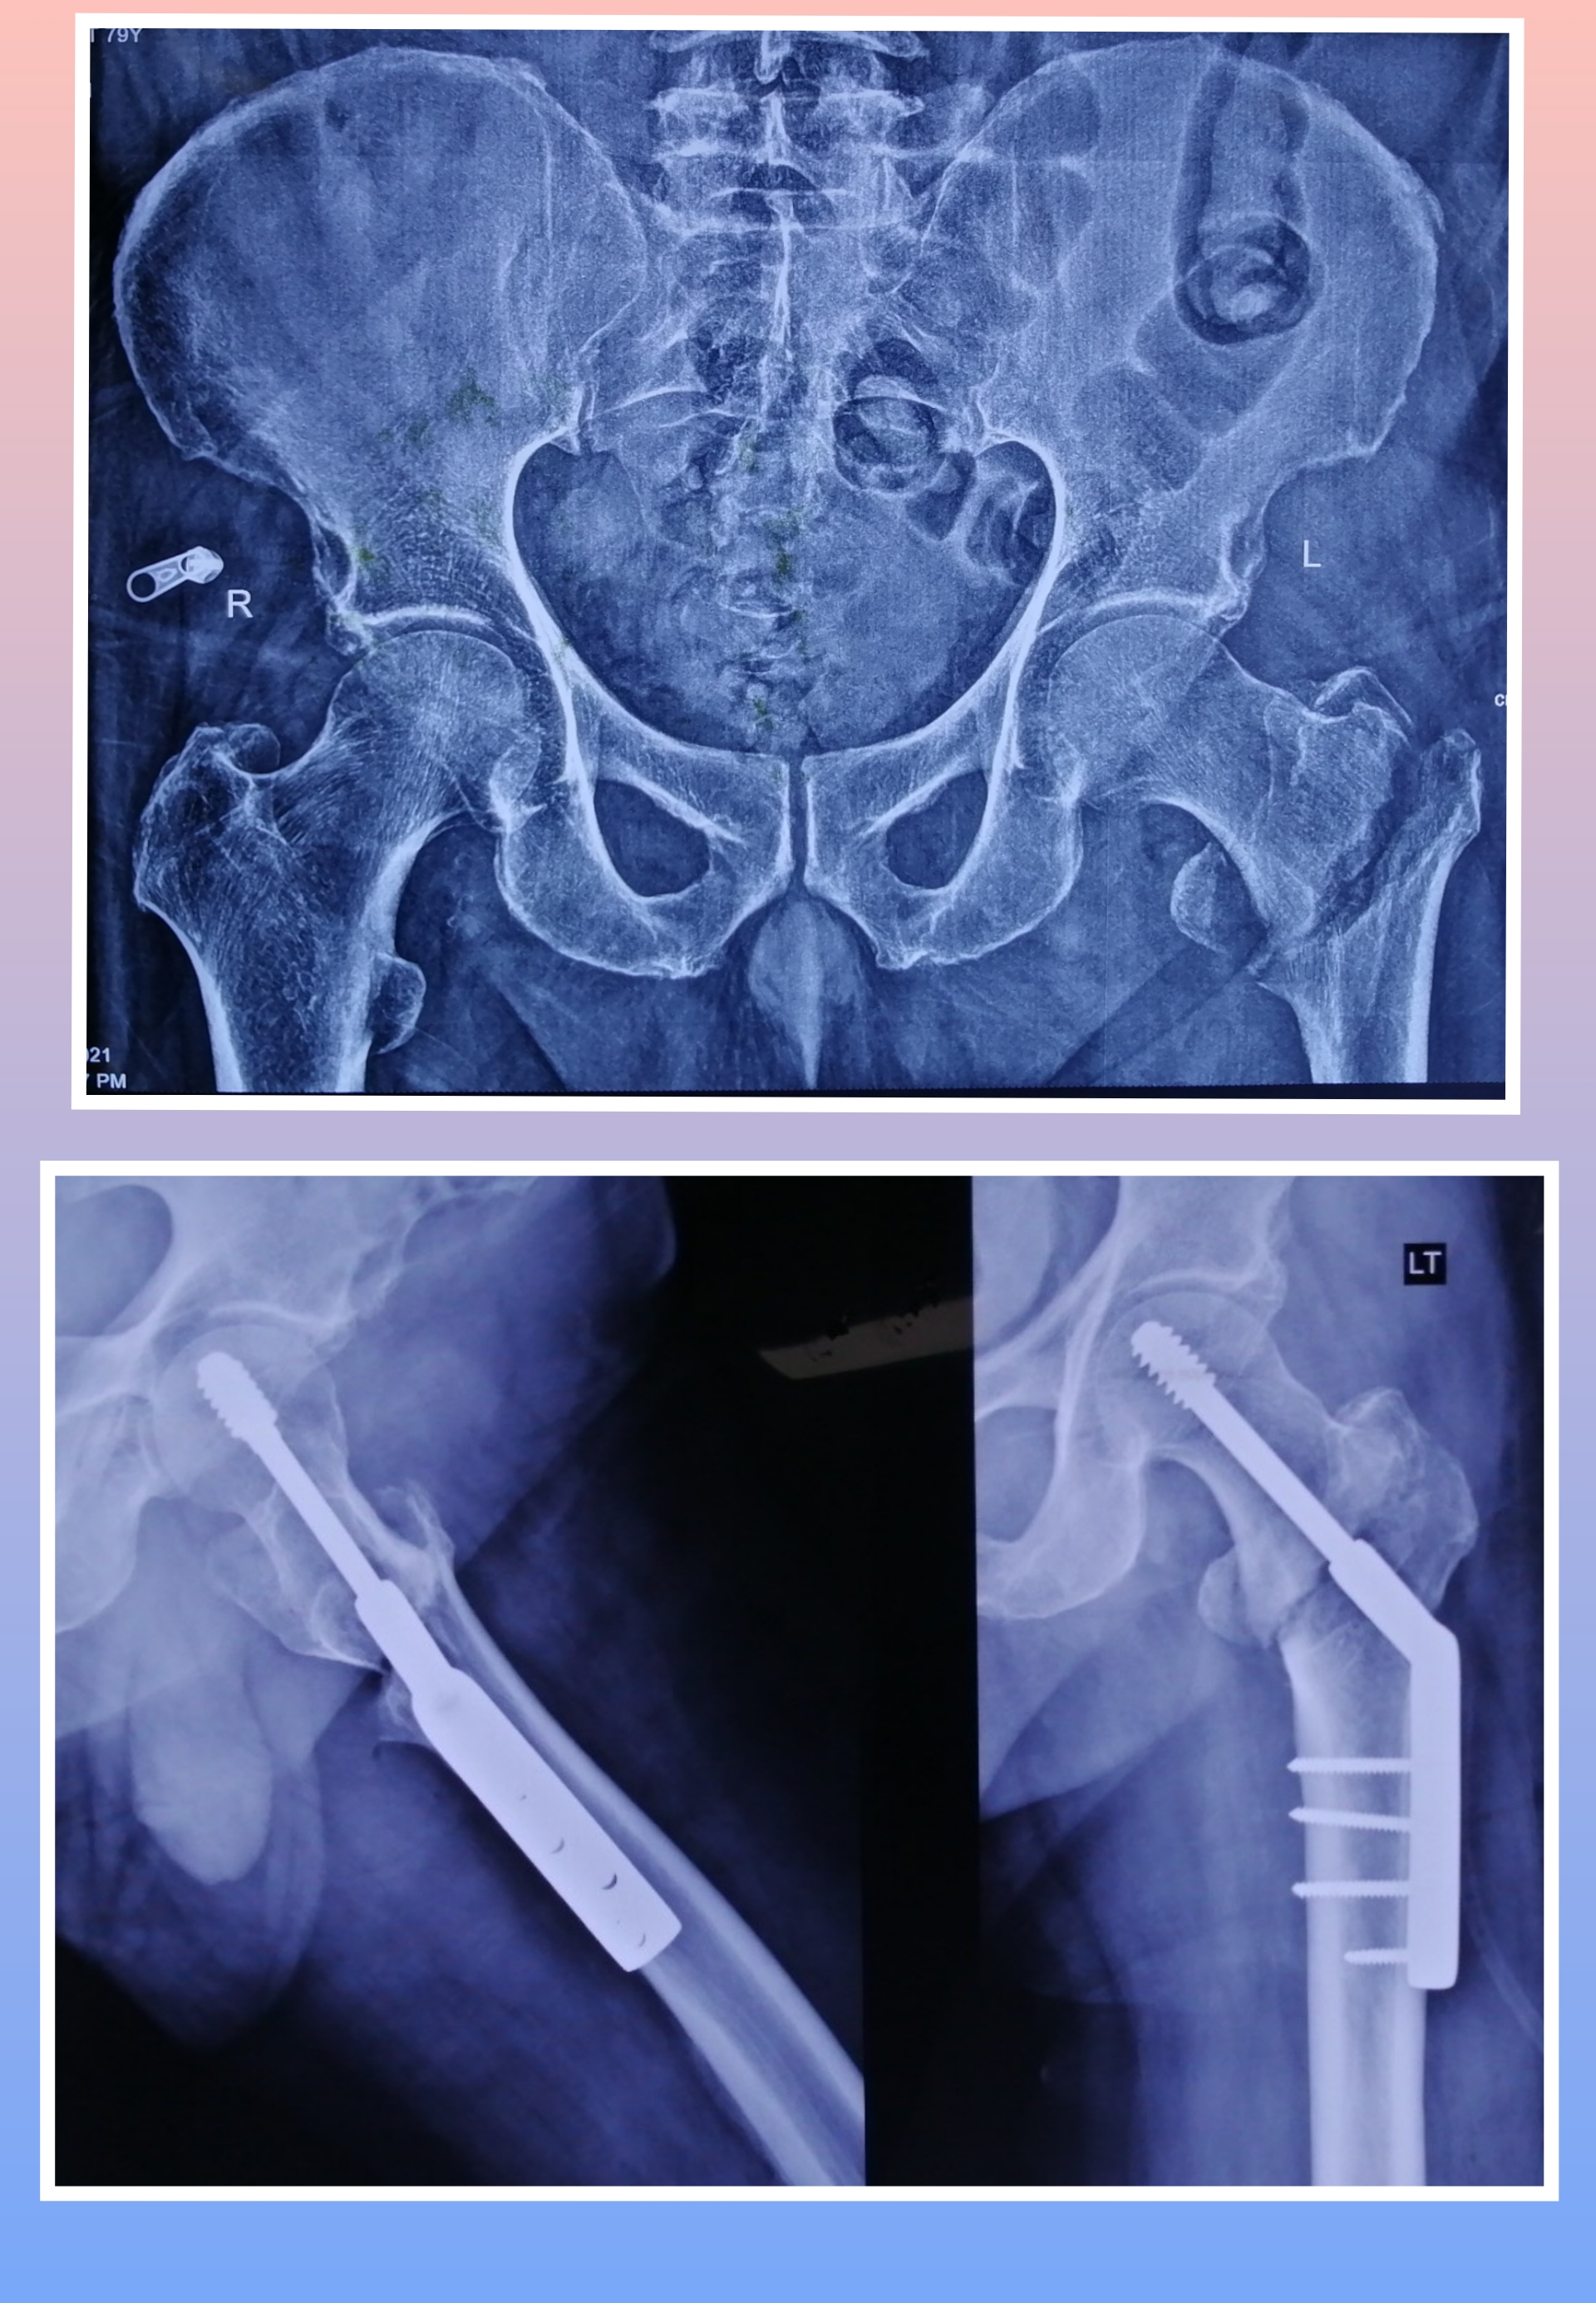

X-ray

Warning: Graphic Content

The following section contains graphic images of surgical procedures. These images are intended for educational purposes and may be disturbing to some viewers. Viewer discretion is advised.

Surgeries